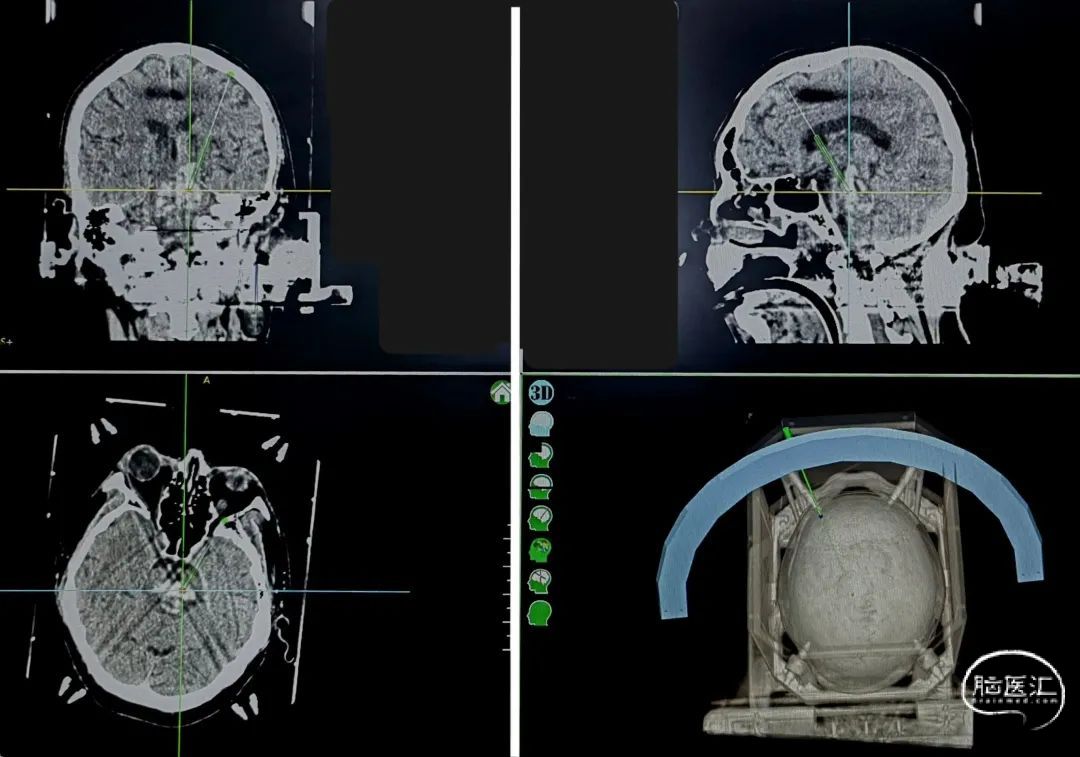

床旁卧位安装头架

脑干血肿头架位置要足够低

CT扫描后测算脑干血肿穿刺靶点及路径

一口双孔,平行植入脑室引流管,测算脑室引流管植入靶点

双靶点

脑室及血肿腔平行双管